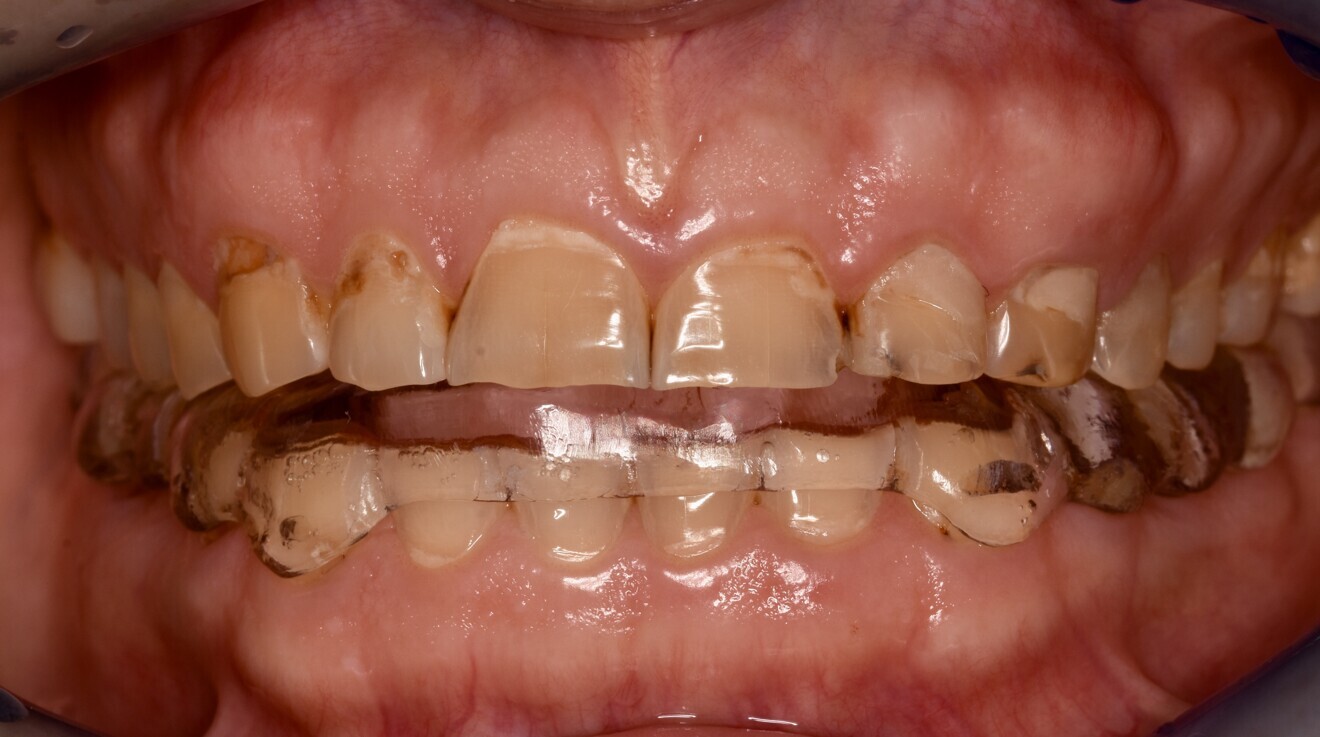

Fig. 1a: Initial situation. Recognisable loss of vertical dimension in the frontal view.

The clinical and radiographic examination revealed pronounced erosive defects on all teeth (Figs. 1a-f). To prevent nocturnal wear of the remaining tooth structure, an occlusal splint had been prepared by the patient’s general dentist in the past. Quick screening for temporomandibular disorder using the tool developed by the German Society of Craniomandibular Function and Disorders was carried out and revealed no functional abnormalities. The diagnosis was generalised, highly pronounced erosion due to exogenous acid (cola), abrasion and attrition with decreased OVD, multiple carious lesions, dentine hypersensitivity, gingivitis and compromised aesthetics.